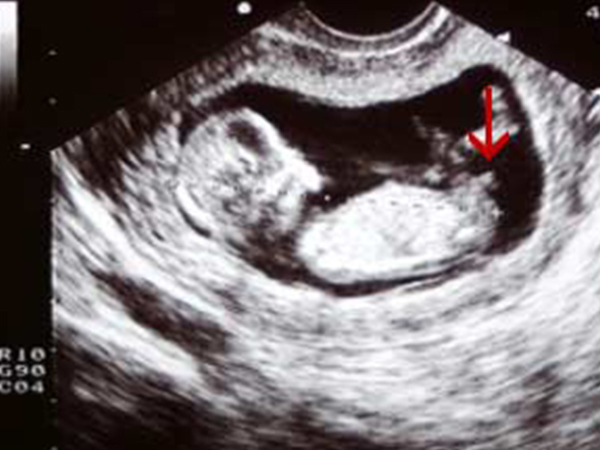

在说到nub点的时候相信有很多准父母并不知道这代表的是什么,其实nub点是宝宝的生殖节,在女性怀孕11周以后,两腿之间的生殖节就会开始发育。由于生殖节在孩子的两腿之间,因此一些看不懂产检报告的人会很容易将腿认成生殖节,导致生男生女的判断失误。

在nt检查的时候,能拍到宝宝的nub点,通过nub点看男女是目前比较流行的一种方法,下面就具体讲一讲如果通过nub点判断腹中宝宝的性别。

1、nub点如果和脊柱线的位置呈现的角度大于30度,证明会生男孩;nub点如果和脊柱线的位置呈现的角度小于30度,则暗示生女儿;

2、如果nub点上翘,屁股也微微上翘,后背脊柱成圆弧状,则暗示生男孩;如果nub点比较平,脊背也比较平,则暗示生女孩。

nub点看男女的准确度比较高,一般来说怀孕11周时,该方法的准确率为48%;怀孕12周时,该方法的准确率为91%;怀孕13周时,该方法的准确率为94%。对于好奇胎儿性别的准父母来说,该方法值得尝试。